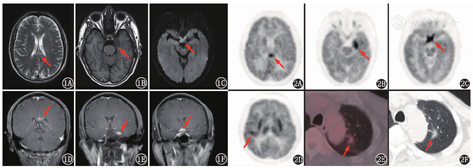

患者男,60岁,主诉性格改变、嗜睡5个月,加重伴视力下降2个月。患者5个月前出现情绪烦躁、易怒、言语减少、嗜睡,伴间断性头晕,未予特殊诊治。2个月前出现左眼视力下降,脾气更加暴躁,反应较前明显迟钝。头部增强MRI示左侧颞叶内侧、左侧基底节区、胼胝体、视交叉多发异常信号。外院曾考虑视神经脊髓炎(neuromyelitis optica, NMO)谱系疾病,予泼尼松及静脉丙种球蛋白治疗,未见好转。20余天前右眼视力下降,双眼均有胀痛感,头晕、嗜睡加重。复查头部增强MRI提示:左侧颞叶内侧、胼胝体、视交叉多发异常信号,T1加权成像(weighted imaging, WI)呈低信号,T2WI呈稍高信号,T2液体衰减反转恢复序列(fluid attenuated inversion recovery, FLAIR)呈高信号,信号较均匀,增强明显均匀强化(图1)。血WBC计数、红细胞沉降率、C反应蛋白、肿瘤标志物正常;血抗Ro-52抗体弱阳性(+),抗线粒体M2型抗体阳性(++),选择性结合水通道蛋白-4(-),白细胞介素(interleukin, IL)-6 2.4(括号内为正常参考值范围,下同;<5.9) ng/L,IL-10 36.1(<9.1) ng/L。行腰椎穿刺,脑脊液压力9.5 cmH2O(1 cmH2O=0.098 kPa),WBC计数10(0~8)×106/L,蛋白质、乳酸、免疫球蛋白(immunoglobulin, Ig)G寡克隆区带(oligoclonal bands, OB)(-),IgG合成率3.5(-9.9~3.3) mg/d,IL-6 6.8(<5.9) ng/L、IL-10 158.0(<9.1) ng/L,病原学(-),抗神经抗原抗体、抗神经节苷脂抗体(-)。

鉴于颅内有多发病变,为评估颅内病变性质,行18F-FDG PET/CT全身显像(图2)。18F-FDG PET/CT图像可见胼胝体体部、左侧颞叶代谢增高灶(图2A,图2B),SUVmax 20.0;视交叉增粗伴代谢增高(图2C),SUVmax 23.9;右侧外侧裂区域皮质代谢增高(图2D),SUVmax 15.2(该处病变头增强MR未见显示)。躯干PET/CT另见左肺上叶混合密度磨玻璃结节,大小1.8 cm×1.1 cm,SUVmax 2.1(图2E,图2F)。本例主要病变位于颅内,累及脑实质皮质及皮质下、白质、视神经,病变均位于幕上,病灶代谢均增高,CT呈等密度,密度较均匀,无明显占位效应,周围未见低密度水肿带,MR信号较均匀,增强扫描除右侧外侧裂区域皮质未见异常,余病变明显强化。患者为老年男性,颅内有多发病变且代谢显著增高,鉴别诊断要考虑颅内恶性肿瘤、脑炎、炎性脱髓鞘性病变、颅内感染性疾病等。